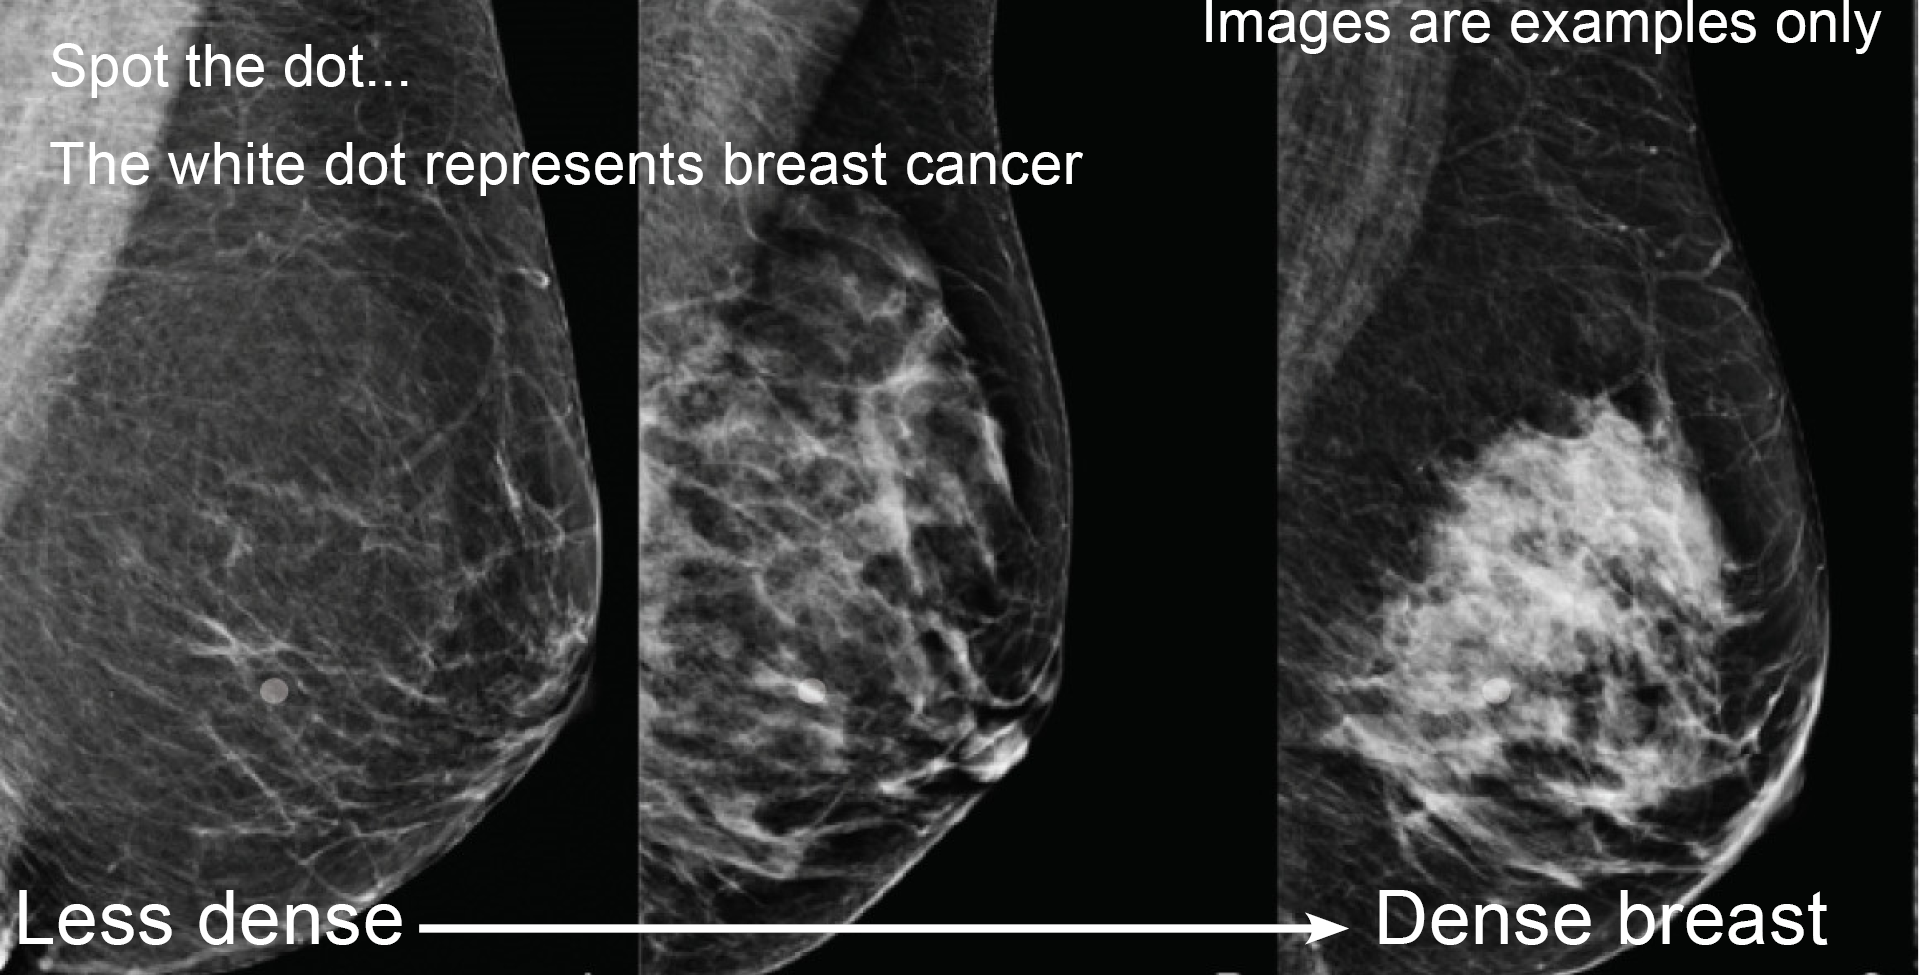

Breast density describes how breasts look on a mammogram. It does not describe how breasts feel on examination by a woman or their doctor. On a mammogram, dense breast tissue appears white whilst fatty breast tissue appears dark. Breast density has the potential to hide breast cancers that also appear white on the mammogram image. Therefore, screening mammograms are a less sensitive test for breast cancer in women with dense breasts.

The greater the breast density, the more white areas on the mammogram, and the less obvious the dot (which is an artificial representation of breast cancer).